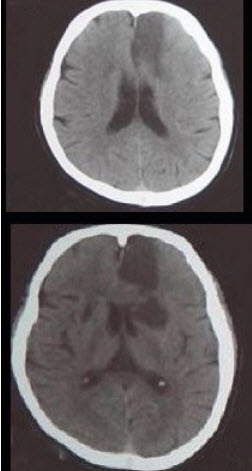

男性,67岁,有糖尿病史5年,高血压病史4年因右侧肢体无力1天入院。查体神志清楚,右侧中枢性面瘫,右上肢肌力4级,右下肢肌力2级。行头颅CT出现如图所示病灶。

(单选题)最可能的诊断是( )

A:脑出血

B:脑梗死

C:颅内感染

D:多发性硬化

E:颅脑肿瘤

第2题,共2个问题

(单选题)该病灶为哪根血管支配( )

A:大脑中动脉

B:脉络膜前动脉

C:大脑后动脉

D:眼动脉

E:大脑前动脉